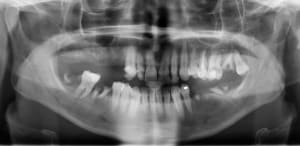

Misen_en_charge_immédiate_implants_et_dents_en_1_seule_intervention_006_dp5adl.jpg